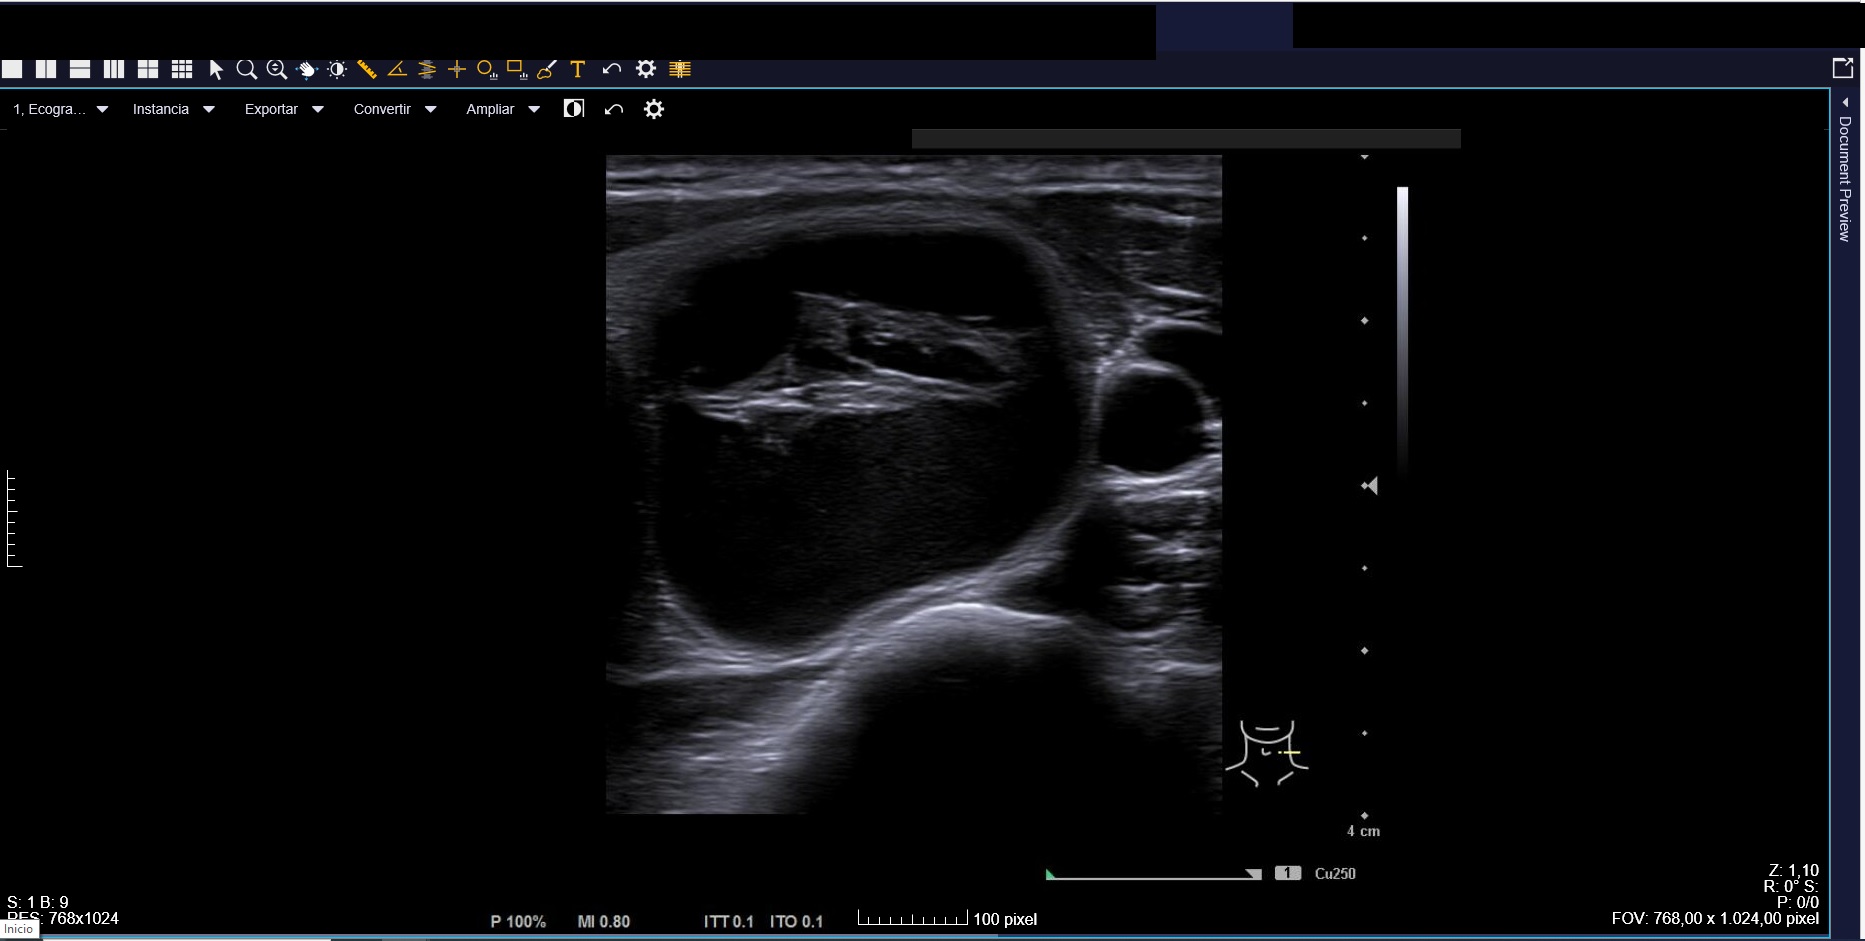

Ecografía clínica: tiroides de tamaño normal con ecoestructura homogénea. En lóbulo tiroideo izquierdo nódulo de 3 cm, anecoico, márgenes bien definidos con imagen hiperecoica en su interior (Imágenes 1, 2 y 3).

Ante clínica y ecografía compatible con hemorragia en nódulo tranquilizamos a la paciente, informándole sobre pronóstico y actitud a seguir. Citamos para seguimiento clínico en 3 semanas, con desaparición del dolor y disminución de tamaño del nódulo.